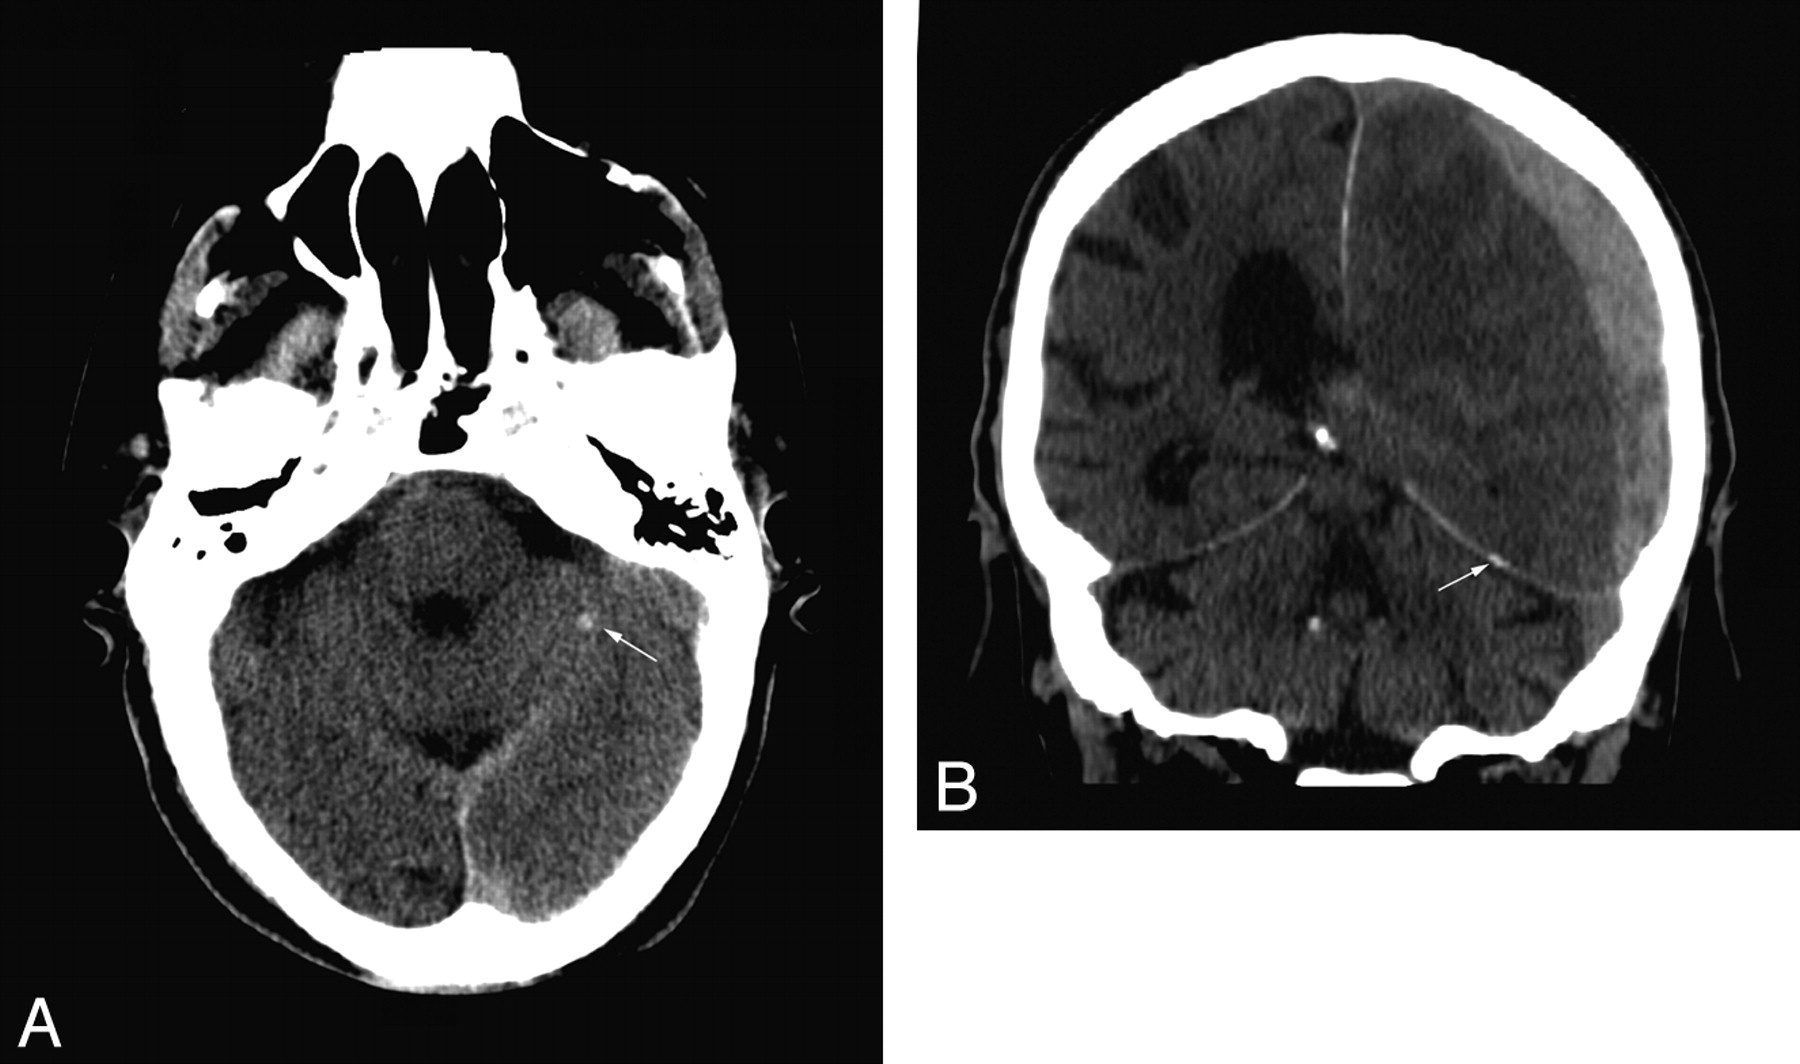

One additional advantage of the coronal images is that the second imaging plane increases specificity by enabling more confident evaluation of questionable findings detected on axial images. Figure 5 shows a potential lesion initially detected on individual axial image review. Subsequent review of the corresponding coronal images shows correlative normal findings, permitting the confident exclusion of pathology.

A, Hyperattenuated focus (arrow) in the left cerebellum interpreted as suspicious for parenchymal hemorrhage. B, Coronal images show that the finding represents tentorial calcification (arrow).